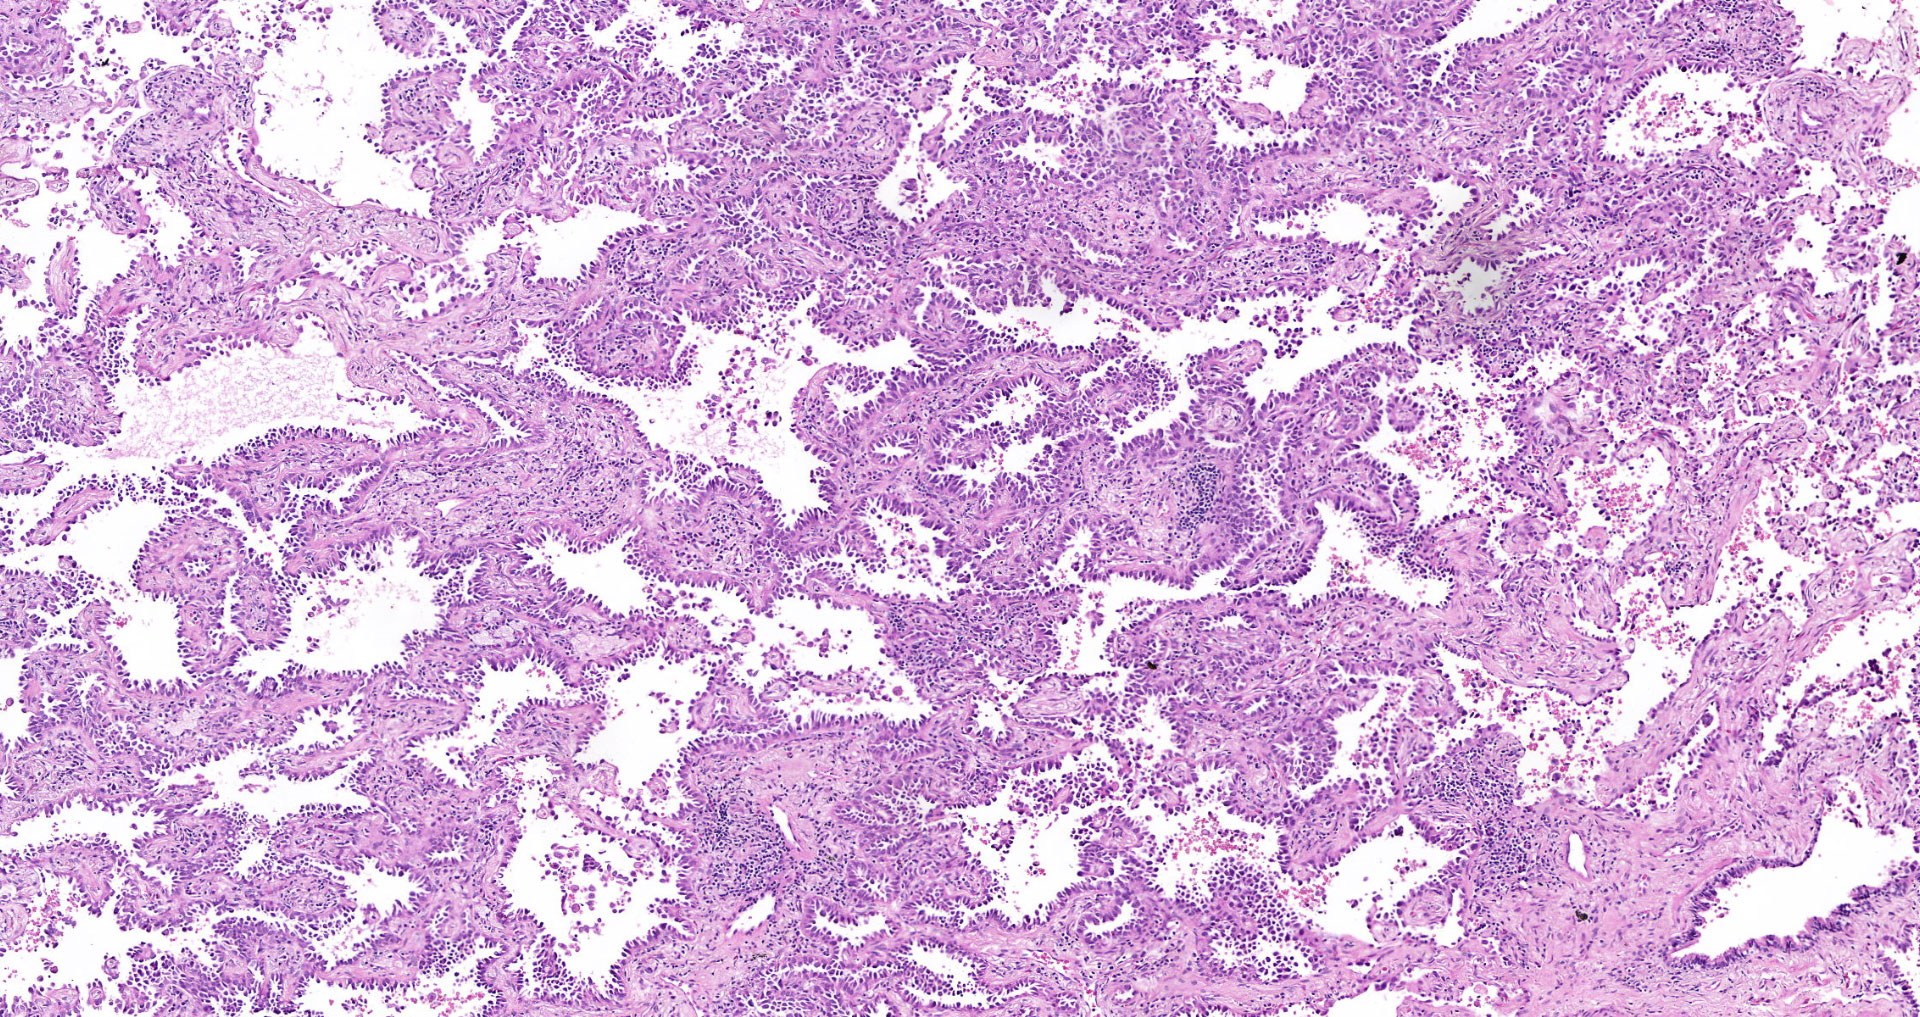

We are happy to announce our new service for our Clients. From the 1st of September, 2020 BioPartners offers you high quality virtual slides (whole slide images) of our banked FFPE samples. Our archive contains more than 1000 scanned images of different types of malignant neoplasms and normal tissues.

Besides, BioPartners offers slide scanning services to medical professionals and organizations at very affordable prices. What you need to do is to send us your glass slides with the completed order form and you will get them back along with the high-resolution and extra-quality virtual slides. Digital slides are either delivered on a DVD (in case of 1-2 glass slides) or an external hard drive. The slide viewing software will be provided as well. Scan type: illumination – bright field, objective magnification – 20x. Approximate size of the digital slide will be between 700MB and 2.5Gb. On your request, your FFPE (formalin fixed, paraffin embedded) or TMA tissue sample can be microtomed and H&E stained.